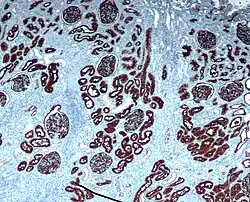

A imuno-histoquímica (IHQ) é um método de localização de antígenos (e.g. proteínas) em tecidos, explorando o princípio da ligação específica de anticorpos a antígenos no tecido biológico.[1] O nome da técnica provém das raízes "imuno", em referência aos anticorpos utilizados no procedimento, e "histo", significando tecido (compare com imunocitoquímica). A coloração imuno histoquímica é amplamente utilizada no diagnóstico de células anormais, tais como aquelas encontradas em neoplasias. Marcadores moleculares específicos são característicos de eventos celulares particulares, tais como proliferação ou morte celular (apoptose). IHQ é também amplamente utilizada na pesquisa básica para compreender a distribuição e localização de biomarcadores e proteínas diferentemente expressas em diferentes partes de um tecido biológico. A visualização de uma interação antígeno anticorpo pode ser obtida de diversas formas. Na situação mais comum, um anticorpo é conjugado a uma enzima, como uma peroxidase, que pode catalisar uma reação que produzirá coloração. Alternativamente, o anticorpo pode também ser marcado com um fluoróforo, como fluoresceína, rodamina, Flúor DyLight ou Flúor Alexa (ver imunofluorescência).

IHQ é uma técnica excelente de detecção, e tem a extraordinária vantagem de se capaz de mostrar exatamente onde uma determinada proteína está localizada no tecido examinado. É também uma forma efetiva de examinar os tecidos. Isso a tornou uma técnica amplamente utilizada nas neurociências, possibilitando que os pesquisadores examinem a expressão de proteínas dentro de estruturas cerebrais específicas. Sua maior desvantagem é que, ao contrário das técnicas de imuno-plotagem (immunoblotting), em que a coloração é checada contra um peso molecular posteriormente, é impossível mostrar na IHQ que a coloração corresponde à proteína de interesse. Por essa razão, anticorpos primários devem ser bem validados em um Western Blot ou procedimento similar. A técnica é ainda mais amplamente utilizada no diagnóstico da patologia cirúrgica para tipagem de tumores (e.g. imunocoloração para e-caderina para diferenciar entre carcinoma ductal in situ (coloração positiva) e carcinoma lobular in situ (não cora)[2].